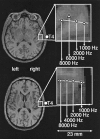

Magnetic source imaging was used to determine whether tonotopy in auditory cortex of individuals with tinnitus diverges from normative functional organization. Ten tinnitus subjects and 15 healthy controls were exposed to four sets of tones while magnetoencephalographic recordings were obtained from the two cortical hemispheres in sequence. A marked shift of the cortical representation of the tinnitus frequency into an area adjacent to the expected tonotopic location was observed. The Euclidean distance of the tinnitus frequency from the trajectory of the tonotopic map was 5.3 mm (SD = 3.1) compared with a distance of 2.5 mm (SD = 1.3) of a corresponding frequency in the healthy controls (t = 3.13, P < 0.01). In addition, a strong positive correlation was found between the subjective strength of the tinnitus and the amount of cortical reorganization (r = 0.82, P < 0.01). These results demonstrate that tinnitus is related to plastic alterations in auditory cortex. Similarities between these data and the previous demonstrations that phantom limb pain is highly correlated with cortical reorganization suggest that tinnitus may be an auditory phantom phenomenon.